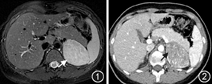

辅助检查:血、尿、便常规及肝肾功能未见异常,电解质:血钠139 mmol/L,血钾3.9 mmol/L,血氯103 mmol/L,二氧化碳结合力(TCO2)24.5 mmol/L,空腹血糖4.6 mmol/L。肾上腺占位功能评估:肾上腺皮质轴:皮质醇节律消失(血皮质醇0∶00 249.23 nmol/L,血皮质醇8∶00 269.38 nmol/L);24 h UFC 149.64 μg,过夜小剂量地塞米松抑制试验不被抑制(服药后血皮质醇280.14 nmol/L);多次查ACTH8∶00<1.1 pmol/L。FSH 4.64 U/L,LH 7.14 U/L,雌二醇251.08 pmol/L,孕酮20.51 nmol/L,睾酮5.59 nmol/L,DHEAS 7.36 μmol/L,17α-OHP 15.24 nmol/L;中剂量地塞米松抑制试验,睾酮、DHEAS、孕酮均不被抑制(具体见表1)。盐皮质激素:肾素活性(PRA)1.85 ng·ml-1·h-1,血管紧张素Ⅱ 80.15 ng/L,醛固酮560.37 pmol/L(180.0~820.0 pmol/L);肾上腺髓质激素:24 h尿儿茶酚胺:去甲肾上腺素15.54 μg(正常参考值:16.69~40.65 μg),肾上腺素2.27 μg(正常参考值:1.74~6.42 μg),多巴胺163.02 μg(正常参考值:120.93~330.59 μg);骨龄相:骨龄18~20岁。子宫双附件超声检查:未见子宫内膜回声,肌层回声均;子宫小(2.6 cm×2.9 cm×1.0 cm),幼稚子宫,左卵巢3.1 cm×1.5 cm,右卵巢2.1 cm×1.1 cm。肾上腺增强CT(图2):左侧肾上腺可见一软组织密度影,大小约50 mm×70 mm,增强扫描可见明显强化,边缘光滑。生长抑素受体显像+腹部CT:左肾上腺软组织占位,生长抑素受体表达轻度不均匀增高。全身骨显像:未见明显异常。正电子发射计算机断层显像(PET/CT):左肾上腺区见一巨大软组织团块,大小5.1 cm×5.3 cm×5.3 cm,平均标准摄取值(SUV)3.5,最高SUV 6.0;左肾上腺区代谢异常增高软组织团块,不能完全除外恶性病变。